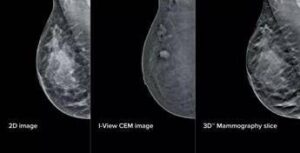

(Adnkronos) - All'azienda ospedaliera San Camillo-Forlanini di Roma la mammografia diventa 'intelligente'. Grazie all'integrazione di intelligenza artificiale e mammografi di...